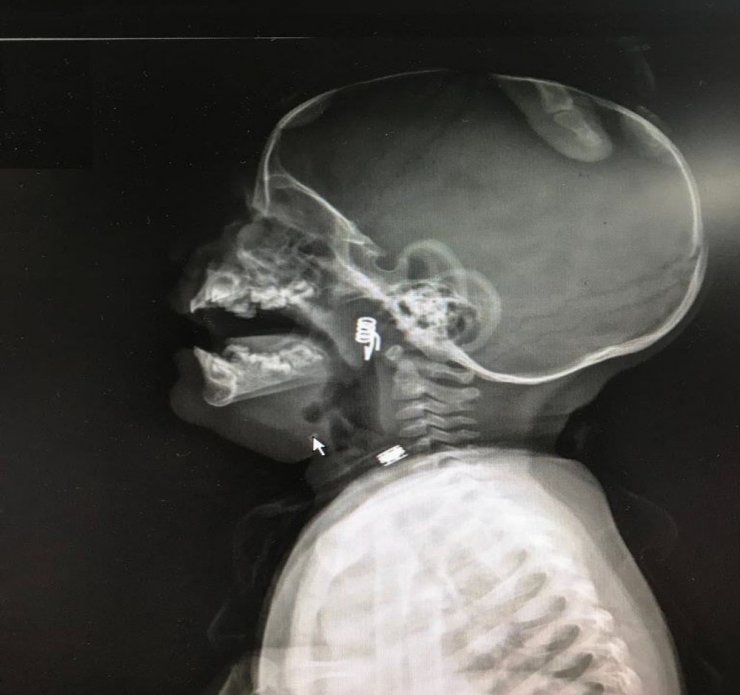

Nevşehir'in Derinkuyu ilçesinde ikamet eden Yılmaz ailesinin henüz 1 yaşındaki bebekleri Özlem İlayda Yılmaz elinde oynadığı mandalı ikiye ayırarak yayı boğazına kaçtı. Baba Yaşar Yılmaz, olayı fark eder etmez kızının boğazına kaçan yayı çıkartmaya çalıştı. Baba Yılmaz tarafından yay çıkartılamayınca aile hemen Nevşehir Devlet Hastanesi Acil Servisine başvurdu. Nöbetçi doktorlar tarafından ilk müdahalesi yapılan minik Özlem, Kulak Burun Boğaz Uzmanı Dr. Ahmet Cevatzade tarafından hemen ameliyatı alınmasının ardından boğaza kaçan yay çıkartıldı.

Baba Yaşar Yılmaz kızının kontrolü için geldiği Devlet Hastanesinde olayı anlatırken kızımın yaşamasını "Önce Allah sonra doktorlarımız sağladı" dedi. Baba Yılmaz, "O gün akşam saatlerinde çocuğum elinde mandal yayı ile oynarken mandalı ikiye ayırıp yayı sökmüş. Ağzına alıp yay ile oynadığını fark ettim. O an hemen parmağımla müdahale ettim ama yayı çıkartamadım. Yay boğazın ilerisine kaçmış. Hemen Nevşehir Devlet Hastanesi Acil Servisine geldik. Acil doktorlarımız çocuğumun filmlerini çekti. Hocamız sağ olsun hemen müdahale etti. Nevşehir Devlet Hastanesi çalışanlarına çok teşekkür ederim" dedi.

Boğazına mandal yayı kaçmasının ardından Kulak Burun Boğaz Uzmanı Op. Dr. Ahmet Cevatzade tarafından ameliyatla boğazına kaçan mandal yayı çıkartıldı. Konuya ilişkin açıklama yapan Dr. Cevatzade, minik Özlem'in sağlık durumunun son derece iyi olduğunu belirterek, " Şuanda çocuğumuzun sağlık durumu gayet iyi. Çocuğumuz şanslıydı. İlk mandalın yayını yuttuğunda babasının müdahalesiyle yay hava yoluna kaçmamış o yönden çok şanslıydı. Çocuk acile getirdiklerinde hemen ameliyata alarak yayı çıkarttık. Şuanda durum çok iyi. Bu tip yabancı cisimler özellikle hava yolunda çok büyük sıkıntılar yaşatıyor. Aileler bu tip şeyler ellerine vermesinler" şeklinde konuştu.